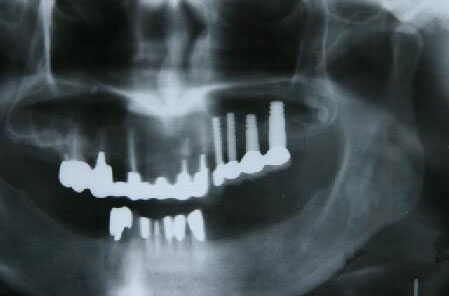

インプラント埋入手術直後のエックス線写真

・骨が薄いので埋入手術後4本のインプラント体をスーパーボンドで固定

・再結晶化HAコーティング施されたインプラントフィクスチャーを使用したため自家骨の移植や

人工骨の添加を行わないで直接埋入